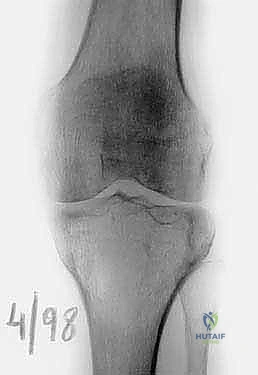

* ورم الخلايا العملاقة (Giant Cell Tumor - GCT): هو المثال الأبرز في هذه الفئة. ينشأ غالباً في نهايات العظام الطويلة بالقرب من المفصل (مثل الظنبوب القريب). في الحالات المتقدمة التي يدمر فيها الورم القشرة العظمية وسطح المفصل، يصبح الاستئصال الكامل وإعادة البناء بالطرف الصناعي هو الخيار الأمثل لمنع عودة الورم (Recurrence).

| الكسور المرضية (Pathological Fractures) | كسر يحدث في العظم نتيجة إصابة بسيطة جداً لا تسبب كسراً في العظم السليم (مثل التعثر الخفيف). يحدث لأن الورم أضعف بنية العظم. | طوارئ طبية |